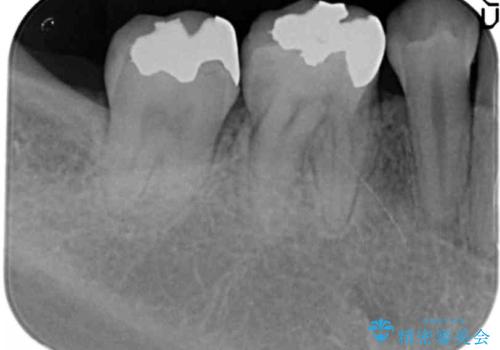

- 矯正治療が終了し、目立つ銀歯を白くやりかえたいと来院されました。

長期的な予後の期待できる銀歯を除去しセラミックインレーによるやり替えを計画します。